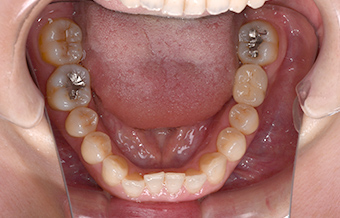

before

| ご相談内容 | 「歯を抜いたところにインプラントを入れたい」とご相談いただきました。 |

| カウンセリング ・診断結果 |

抜歯後、数カ月が経過しており骨や歯茎の状態も良好でしたので、インプラント可能と診断いたしました。 |